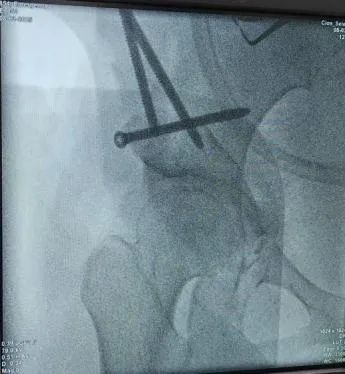

图5-6:术中截骨